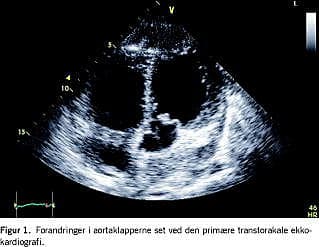

Patienten blev venyleret, og der blev opstartet intravenøst givet behandling med ampicillin, gentamicin og metronidazol. Patienten havde forhøjede infektionsparametre med et leukocytniveau på 15,4 mia./l og C-reaktivt protein på 257 mg/l. De øvrige blodprøver var normale. Urinstiks var blank. Dagen efter fremkom der bloddyrkningssvar med vækst af Streptococcus pneumoniae i fire af fire kolber, og den antibiotiske behandling blev skiftet til intravenøst givet penicillin. Cervixpodning var negativ. Ved et øre-næse-hals-tilsyn fandtes normale forhold i næse og svælg. Podning fra rhinopharynx og næse bortkom efterfølgende i posten. Patienten var på femtedagen i klinisk bedring med faldende infektionstal, men fortsat svingende temperatur. Ved fornyet objektiv undersøgelse rejstes der mistanke om systolisk mislyd. Ved kardiologisk tilsyn fandt man splinters på syv af ti fingre, og ved bedside transtorakal ekkokardiografi sås suspekte strukturer i aortaklapperne med let til moderat aortainsufficiens (Figur 1). Patienten blev overflyttet til kardiologisk afdeling mhp. monitorering. En transøsofagealekkokardiografi viste svær endokarditis med vegetationer i aorta- og mitralklapperne med abscedering i aortaroden og svær aortainsufficiens og moderat mitralinsufficiens. Patienten var hæmodynamisk stabil.